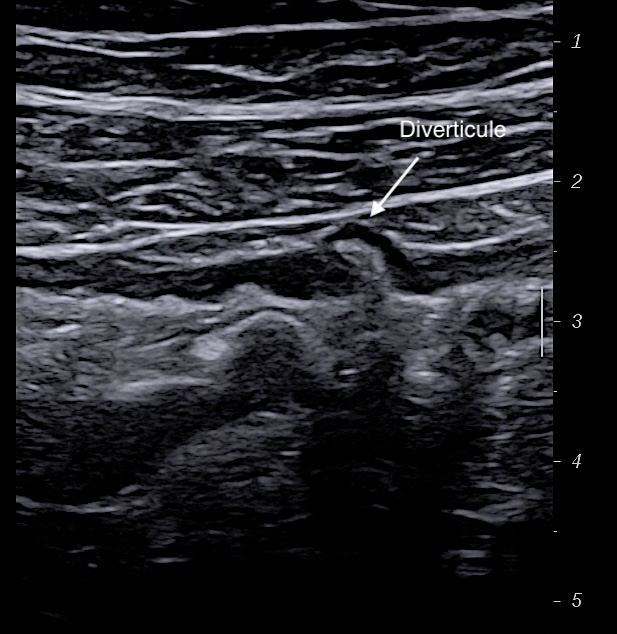

C'est plutôt un diagnostic différentiel des MICI car on l'observe surtout au niveau du sigmoide dans la maladie diverticulaire.

En basse fréquence la musculeuse épaissie hypoéchogène souligne les parois du sigmoide

Epaississement musculeuse et image diverticulaire

Musculeuse sigmoidienne épaissie paroi non inflammée